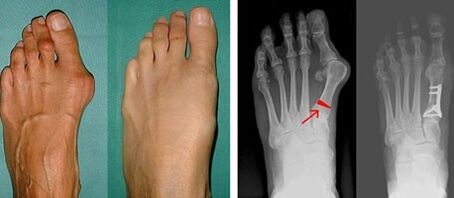

Valgus deformity of the first leg most often affects older women, but it also affects men.A deformed base of the thumb does not look aesthetically pleasing.In this case, a person feels physical discomfort, and in the advanced stage - pain.Big toe deviation is the result of uneven body load on the foot.Such changes have a harmful effect on the feet and other fingers.

If the visual examination and X-rays do not give any results, the patient is referred to plantography to identify possible flat feet.This method involves taking impressions of the feet based on shoes or insoles with orthopedic properties for the patient.The patient is then prescribed podometry.This method uses computer analysis to determine the standing pressure of a person's weight.The results of advanced diagnostics are the basis for choosing a treatment method for curvature of the first and second finger.

At the first stage of determining the valgus of the big toe and little toe, the doctor conducts a visual examination.In this way, it determines the stage of development of the pathology.X-rays and plantography are prescribed to determine detailed changes in joints.